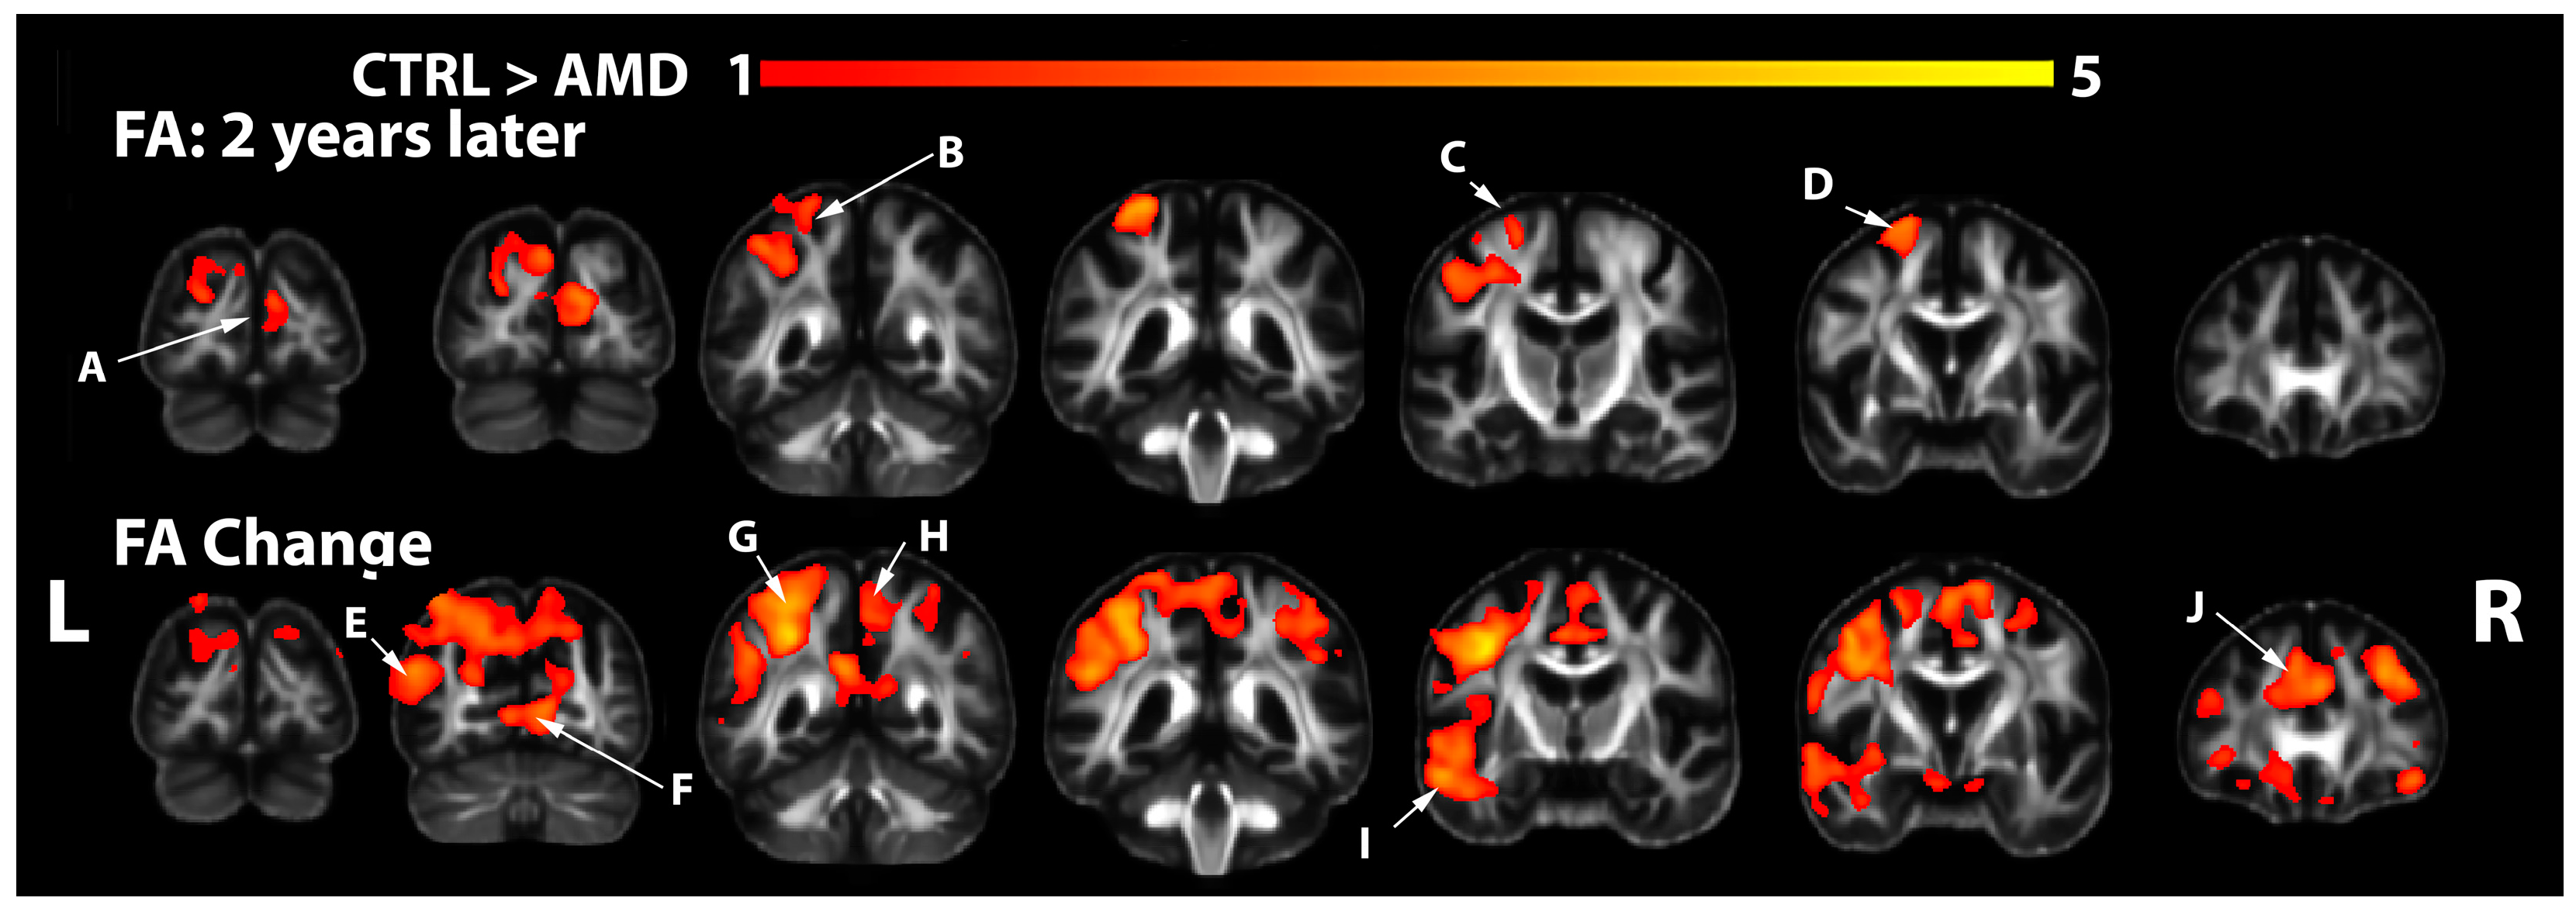

3.2. FA Changes in AMD Participants